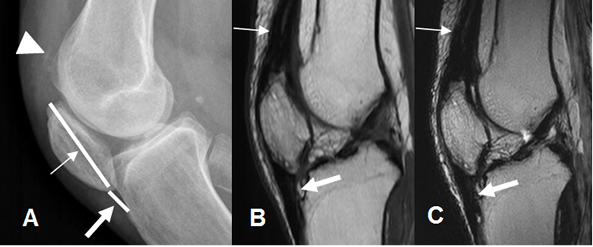

Fig 162. Inestabilidad patelar vertical.

A: Rx lateral. Patela baja. La longitud de la patela (Flecha delgada), es mayor que el espacio entre su polo inferior y el sitio de inserción. (Flecha gruesa). Se aprecian calcificaciones anteriores, por tendinitis crónica. (Punta de flecha).

B: RM sagital en T1 y C: RM sagital en T2. Engrosamiento de los tendones del cuadriceps (Flecha delgada) y patelar (Flecha gruesa), por tendinitis crónica.